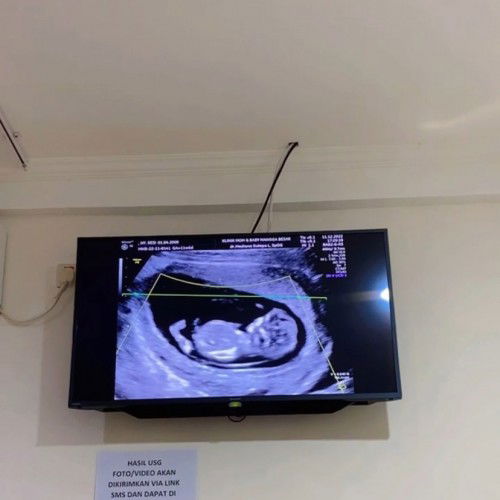

Moms disini usia kehamilan 14weeek ud ngerasain apa aja ya? Terus kondisi perutnya udh sebesar apa? Apakah masih rata kaya aku apa sdh mulai membentuk 🥰#firstmom ini kmren usg pas usia 12week mams doain semoga sehat2 yaa 💗 semangat para moms dsini